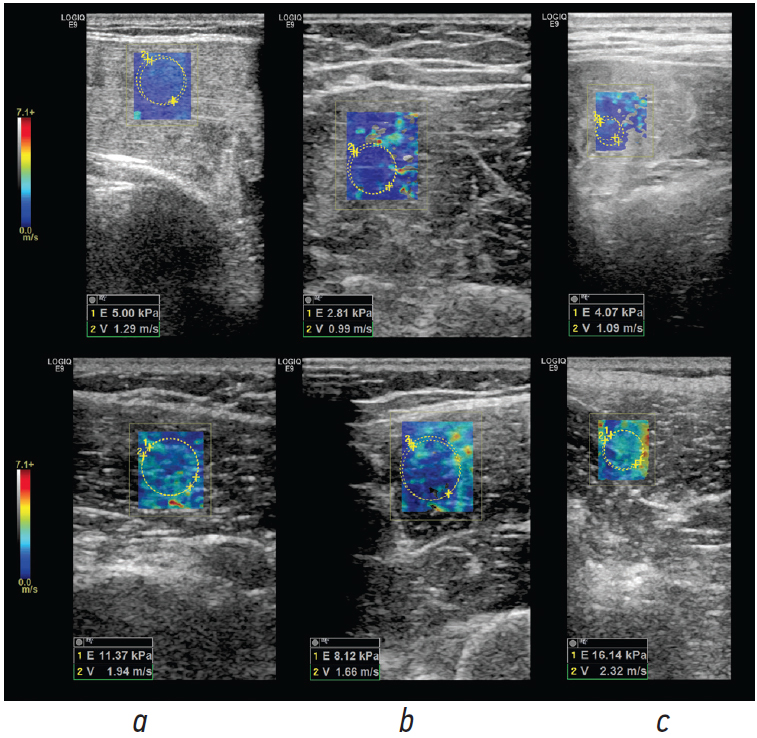

When comparing the muscle tissue stiffness coefficients in m/s and kPa, values in rhabdomyolysis were statistically significantly different both from other diseases manifested by muscle edema (Mann–Whitney U-test with Bonferroni correction, p < 0.001) and from the control group (Mann–Whitney U-test with Bonferroni correction, p < 0.001) downward (Fig. 2). Moreover, lateral wave velocity and stiffness in muscle edema did not statistically significantly differ from the control group, with p = 0.583 and p = 0.117, respectively (Mann–Whitney U-test with Bonferroni correction).

Fig. 2. Echograms with measurement of SWE parameters; upper row, rhabdomyolysis; lower row, control group: a, back extensor muscles; b, external vastus muscles; c, pectoralis major muscles

Thus, SWE can be used for diagnosing rhabdomyolysis; however, it does not allow the differentiation of other forms of muscle edema from normal muscles.

The evaluation of data in the control group revealed an abnormal distribution of SWE indicators. The median values and interquartile range for the lateral wave velocity V were 2.03 [1.72; 2.64] m/s, and those for stiffness E were 13.22 [10.09; 22.41] kPa.